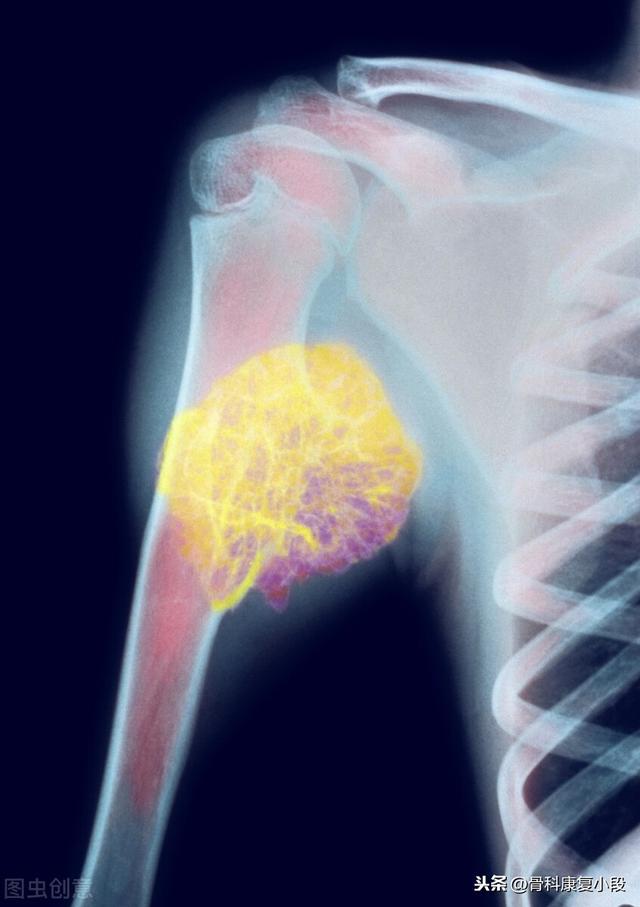

骨転移で起こる症状にはどのようなものがありますか?最初の症状は痛みです。骨転移を起こした部位は骨が破壊されるために痛みを感じますが、最初ははっきりした症状がなかったり、断続的な痛みだったりしますが、腫瘍が正常な骨をどんどん破壊して徐々に悪くなっていくため、転移部位の痛みも徐々に悪くなっていきます。臨床的には、体のある部分の骨の痛みで、悪性腫瘍の骨転移という症例に出くわすことがあります。以前、ある症例に出会ったのですが、40歳で、肩が痛く、五十肩かと思い、薬用オイルを数日揉んでも改善が見られず、ますます痛みが強くなったので、病院で検査をしたところ、MRIを撮ったところ、肩甲骨が(腫瘍の)かけらに食べられており、骨転移を考え、胸部CTを撮ったところ、右肺に結節があり、生検をして病理検査をしたところ、肺がんの骨転移でした。その内容は以下の通りである。

骨転移部位では、正常な骨組織が破壊され腫瘍組織に置き換わり、腫瘍細胞は常に増殖しているため、多くの骨転移部位で軟部組織の腫瘤影が見られ、腫瘤が表在する部位であれば触知することができる。また、腫瘍組織による正常な骨組織の侵食は、正常な骨構造の破壊と脆弱化につながるため、正常な外力下でも骨折が生じることがあり、病的骨折と呼ばれます(下図)。脊椎への転移は、疼痛や病的骨折に加えて、脊髄神経根の圧迫を伴い、感覚障害、筋力低下、場合によっては高カルシウム血症などの症状を呈することもあります。

骨転移で起こる症状を理解しやすくするために3種類の骨腫瘍を紹介

がんの最も顕著な痛みは痛みである。骨腫瘍の場合、特定の検査で偶然見つかるのとは別に、特定の部位の痛みの検査で見つかる。骨腫瘍の発症については、例えば骨肉腫は思春期に多く、骨巨細胞腫は若年成人に多く、骨髄腫は高齢者に多いなど、非常に年齢差があります。次に、骨軟骨腫、骨巨細胞腫、骨肉腫の3つの異なるタイプの腫瘍の特徴についてお話しします。